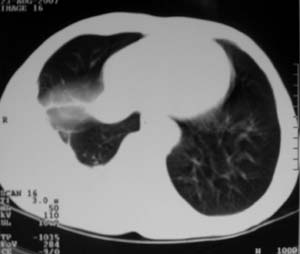

标题: CT9556:男,54岁,包裹性积液,请各位老师会诊其原因! [打印本页]

男,54岁,无任何不是感.体检发现右肺部阴影.现行ct进一步确诊.

周围都钙化了应该不是积液了吧,这样都没有不适感,病史不详